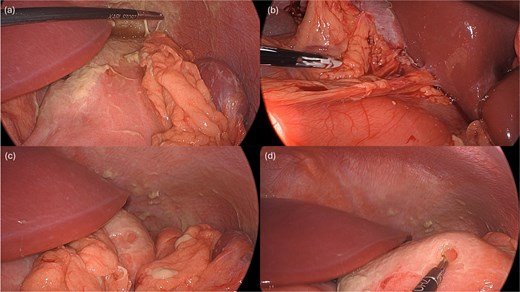

Laparoscopy began with placement of a 5 mm umbilical trocar and two additional 5 mm trocars in the right and left abdomen. Turbid fluid was encountered and suctioned. In the upper-abdomen, significant inflammatory omental adhesions were found against the right upper quadrant and gallbladder. A complex fluid collection with inflammation was identified in the left upper quadrant (Fig. 2). These inflammatory adhesions were carefully dissected using a Cool-SealTM device to visualize the pylorus and duodenum; however, inflammation around the gallbladder prevented full release of these adhesions. Mobilization of the gastrocolic ligament revealed a normal posterior gastric wall. Because inflammatory exudates obscured the anterior stomach and the first and second part of the duodenum, making the perforation’s origin (duodenal or gastric) initially unclear, simultaneous intraoperative-endoscopy was requested for precise localization.

Intraoperative pictures demonstrating the sequelae of the hollow viscus perforation. The pictures in (a) and (b) demonstrate contamination and associated inflammatory adhesions in the left and right upper quadrant, respectively. The pictures in (c) and (d) demonstrate the antral perforation. The tip of the Maryland dissector was able to insert into the perforation (d) to assist with identification of the perforation endoscopically for closure.